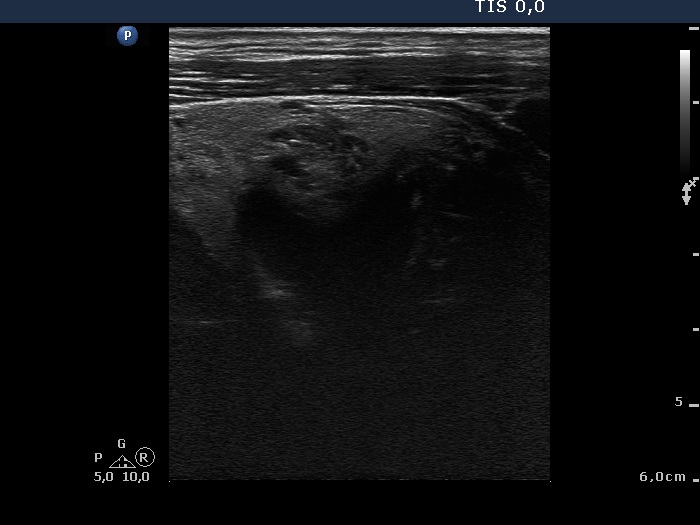

Ultrasonography: The thyroid was echonormal with a few insignificant lesions. There was a large cystic lesion dorsal to the lower third of the right lobe.

After aspiration of 10 ml yellow fluid the size of the lesion decreased from 35x31x42 mm to 29x22x39 mm. The patient refused to aspirate more fluid because her complaints ended.

Final diagnosis: parathyroid cyst.